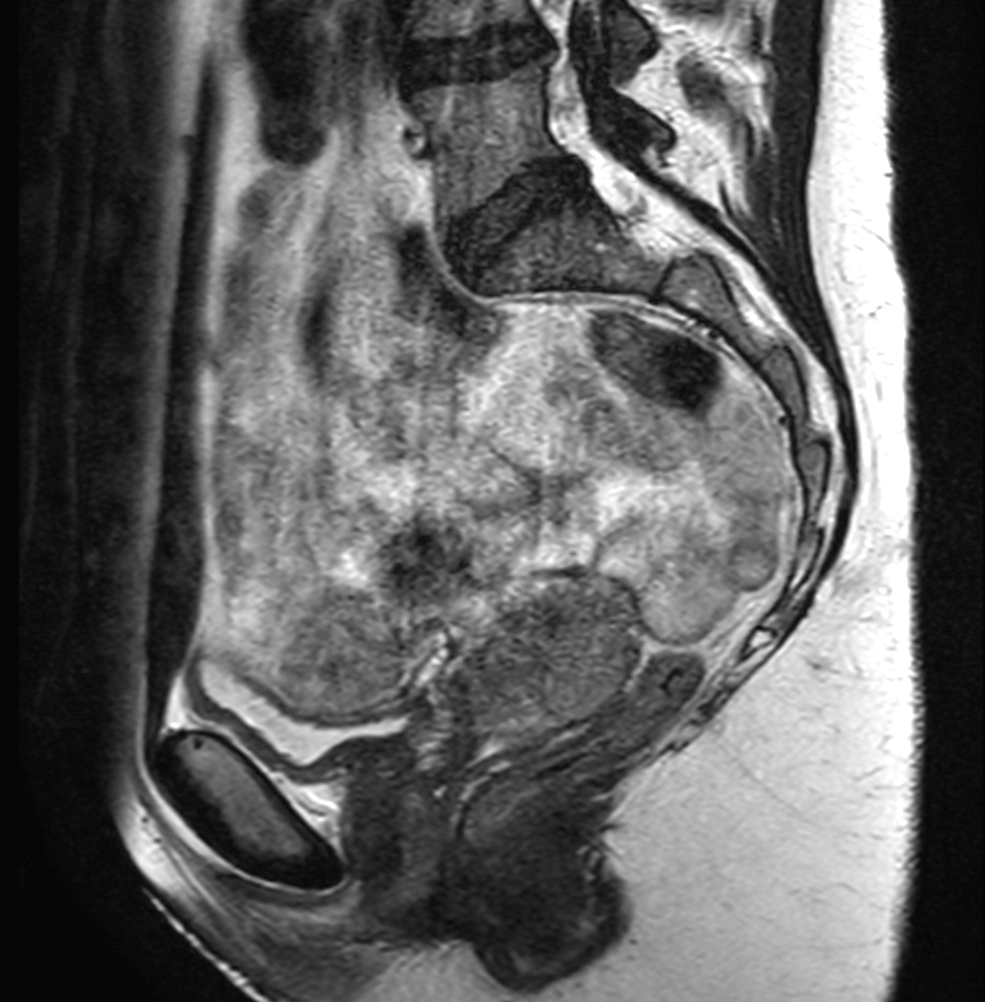

Patient diagnosed with cervical cancer referred for external beam radiotherapy. Three MRIs with different bladder filling were acquired: Half full (mid), empty and full bladder. Patient was imaged at Ingenia MR-RT 1.5T using FlexCoverage Anterior Coil in combination with the integrated Posterior Coil.

Sagital T2w TSE mid